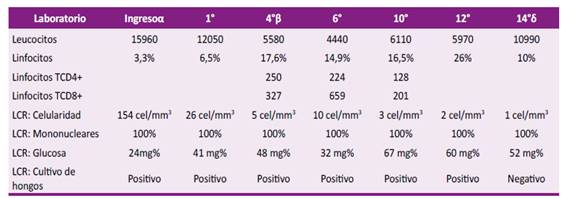

La analítica de ingreso mostró una leucocitosis con neutrofilia y linfopenia relativa y absoluta, resto de los exámenes dentro de parámetros normales (Tabla 1). En la resonancia magnética (RM) cerebral que trajo consigo mostró una lesión en núcleos basales izquierdos sugerente de un infarto cerebral debido a una probable vasculitis infecciosa (Figura 1). Se realizó una punción lumbar obteniéndose líquido cefalorraquídeo (LCR) con características inflamatoria crónica, consumo de glucosa, tinta china positiva, y un cultivo que posteriormente resultó positivo para Cryptococcus spp (Tabla 1). La tomografía de tórax mostró lesiones sugerentes de criptococosis pulmonar (Figura 2). Se diagnosticó criptococosis meníngea confirmada y pulmonar probable, iniciándose tratamiento con anfotericina B desoxicolato (AmBd) y fluconazol vía endovenoso.

Tabla 1 Evolución de resultados laboratoriales durante las 14° semanas de hospitalización.

α: Fase de inducción con anfotericina B desoxicolato (AmBd) más fluconazol. AmBd se suspendió a la 3° semana y continuó solo con fluconazol. β: Reinicio de AmBd, extendiéndose la fase de inducción hasta la 12° semana. δ: Suspensión de AmBd y pase a fase de consolidación con fluconazol únicamente. LCR: líquido cefalorraquídeo; cel: células.

Debido a que la criptococosis meníngea es una complicación frecuente en pacientes inmunosuprimidos por el VIH, y dado el antecedente de conductas de riesgo, se realizaron estudios para descartar la presencia de este virus, resultando negativos en múltiples oportunidades. Entre estos se solicitó un recuento de linfocitos T-CD3 (CD4+/CD8+), evidenciándose una disminución de los linfocitos T-CD4+, con valores normales de los linfocitos T-CD8+, y una relación CD4/CD8 <1. Se repitió este examen semanas posteriores hasta en 2 oportunidades más, con resultados similares (Tabla 1).

Se decidió reiniciar tratamiento con AmBd asociado a fluconazol, y corticoides para el manejo del edema cerebral. Recibiendo una dosis total de AmBd de 2,3 gramos, administrados en un esquema individualizado (infusión interdiaria durante 8 semanas) para minimizar efectos adversos de la medicación. Con evolución clínica, laboratorial (Tabla 1) e imagenológica (Figura 1) favorable, continuando solo con fluconazol vía oral, sin recaídas hasta la publicación del presente reporte.